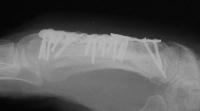

I removed this hardware, and used two mini condylar blade plates at right angles to resecure the distal bone juncture. This allowed more distal purchase while avoiding hardware placement beneath the metacarpal head extensor hood. I replated the proximal bone juncture although it looked clinically healed - not worth taking a chance.

Final result, eight months postop, healed:

Healed.